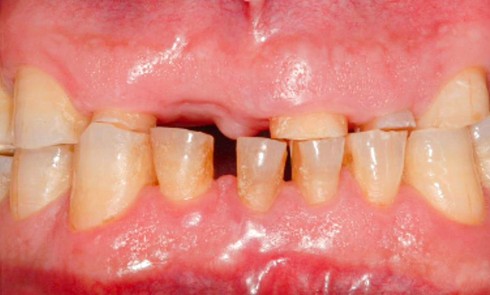

Quelles sont les 7 formes cliniques des épulis ? 1. Épulis inflammatoire (plasmocytaire) Nodule indolore, pédiculé, érythémateux, parfois ulcéré (fig. 1a)....